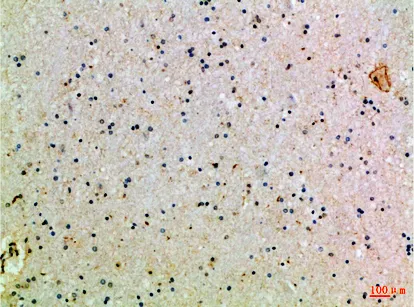

AR-α1D Rabbit Polyclonal Antibody($99/20μL)

Cat: APRab07192

Size1:20μL Price1:$99

Size2:50μL Price1:$118

Size3:100μL Price2:$220

Size4:200μL Price3:$380

Application:IHC-P,IF-P,IF-F,ICC/IF,ELISA

Reactivity:Human,Rat,Mouse

Conjugate:Unconjugated

Optional conjugates: Biotin, FITC (free of charge). See other 26 conjugates.

Gene Name:ADRA1D